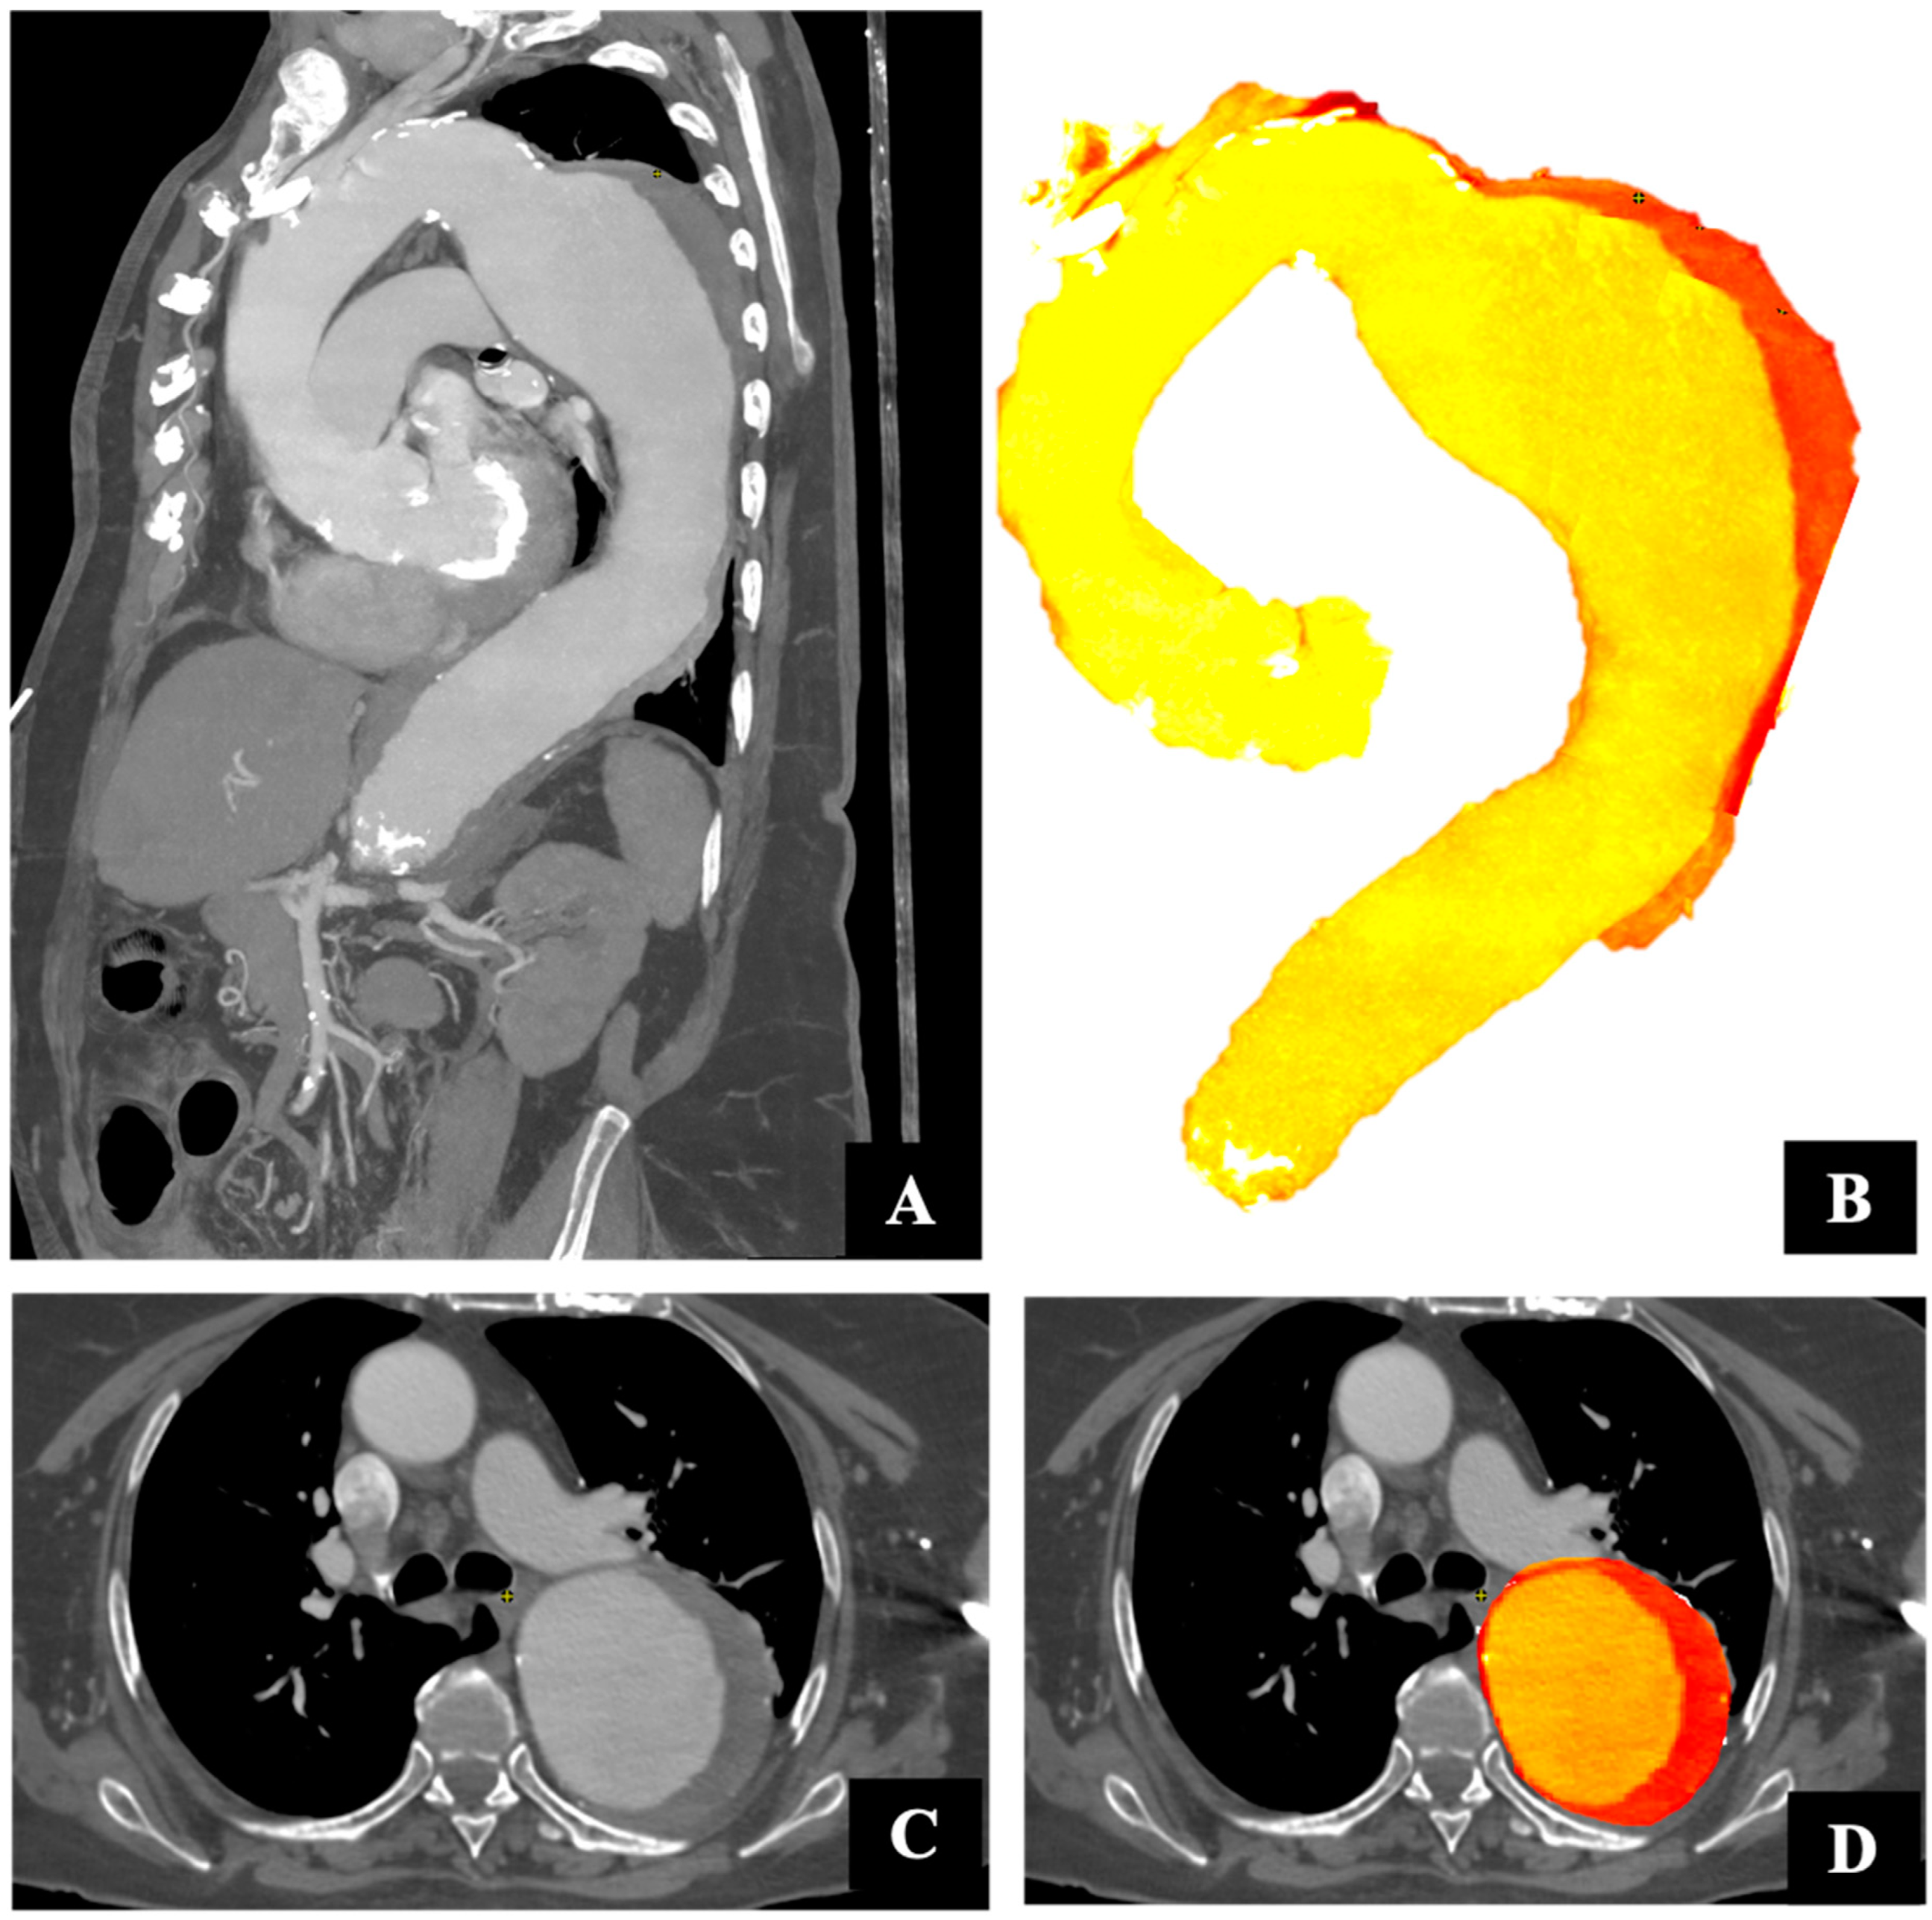

2.3. Image Analysis and Measurement Volume